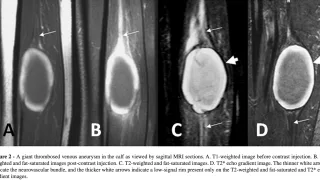

午前の病院での仕事今朝は, 曇.雲が厚く, 部屋の中が薄暗かったので, 電灯を点けました.雨の予報ですが, 午後には上がるとのこと.8時前に病棟に上がって, 8時から朝の病棟回診.昨日, 足関節部の神経鞘腫を摘出した患者さんは, つま先を曲...